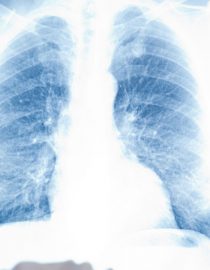

The most common way lupus can affect your lungs is through inflammation of the pleura, the lining that covers the outside of the lungs — this is called pleurisy.

What’s Happening Inside the Lungs?

The double-layered pleura protects and lubricates the surface of the lungs as they inflate and deflate within the rib cage. Normally, a thin, fluid-filled gap — the pleural space — allows the two layers of the pleural membrane to slide gently past each other.

But when these layers become inflamed, with every breath, sneeze, or cough, their roughened surfaces rub painfully together.